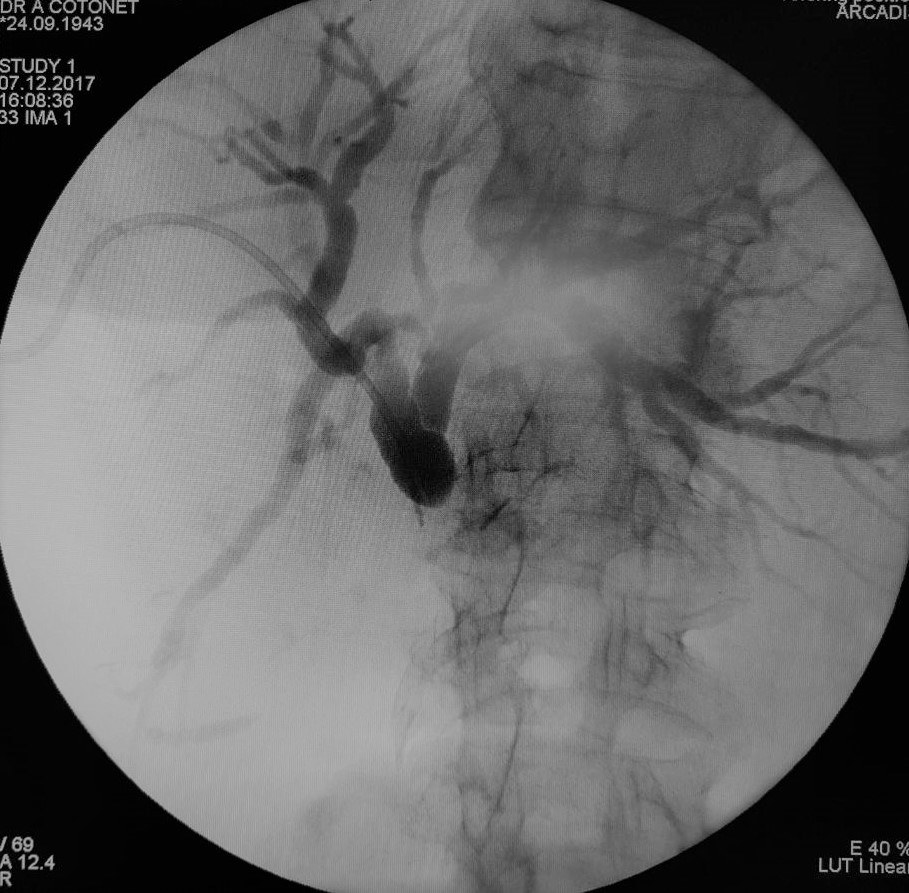

Creşterea siguranţei şi curabilităţii în chirurgia hepatică extensivă a impus dezvoltarea de tehnici, care să asigure funcţionalitatea hepatică a ficatului restant – drenajul biliar preoperatoriu. Scopul drenajului biliar preoperatoriu este de a îmbunătăţi funcţia hepatică şi reduce morbiditatea şi mortalitatea după chirurgie radicală cu hepatectomie majoră, adică rezecţia a mai mult de trei segmente hepatice. Practica arată că rezecţiile hepatice la pacienţii cu icter obstructiv complet şi colangită sunt asociate cu complicaţii severe, dintre care sunt de amintit sângerări intraoperatorii, abcese subfrenice datorate fistulelor biliare şi insuficienţă hepatică. Rolul drenajul percutanat este, pe lângă acela de a obţine o evaluare a extensiei intraductale a carcinomului, cel de a scădea nivelul bilirubinei şi de a permite hipertrofia ficatului dacă se realizează embolizarea venei porte.

Astfel, medicii cabinetului de endochirurgie Cotoneț Alic și Bodrug Roman realizează cu succes acest tip de intervenții deja în mai multe cazuri. Utilajul modern permite cu înaltă precizie puncția ghidată sonografic a căilor biliare urmată la aceeași ședință de drenarea arborelui biliar sub control radiologic.